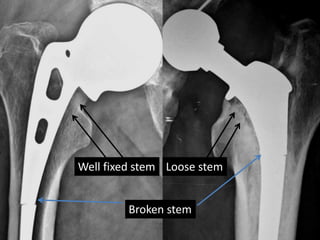

Well fixed stem Loose stem

Broken stem

Observations - THR

• In THR stem brake due to fixed distal part and

loose proximal part.

• Since proximal part is loose, it needs revision.

• In contrast to THR, breakage of AMP stem is

due to loose distal part and a Fixed proximal

part.

Well fixed stemLoose stem Broken stem